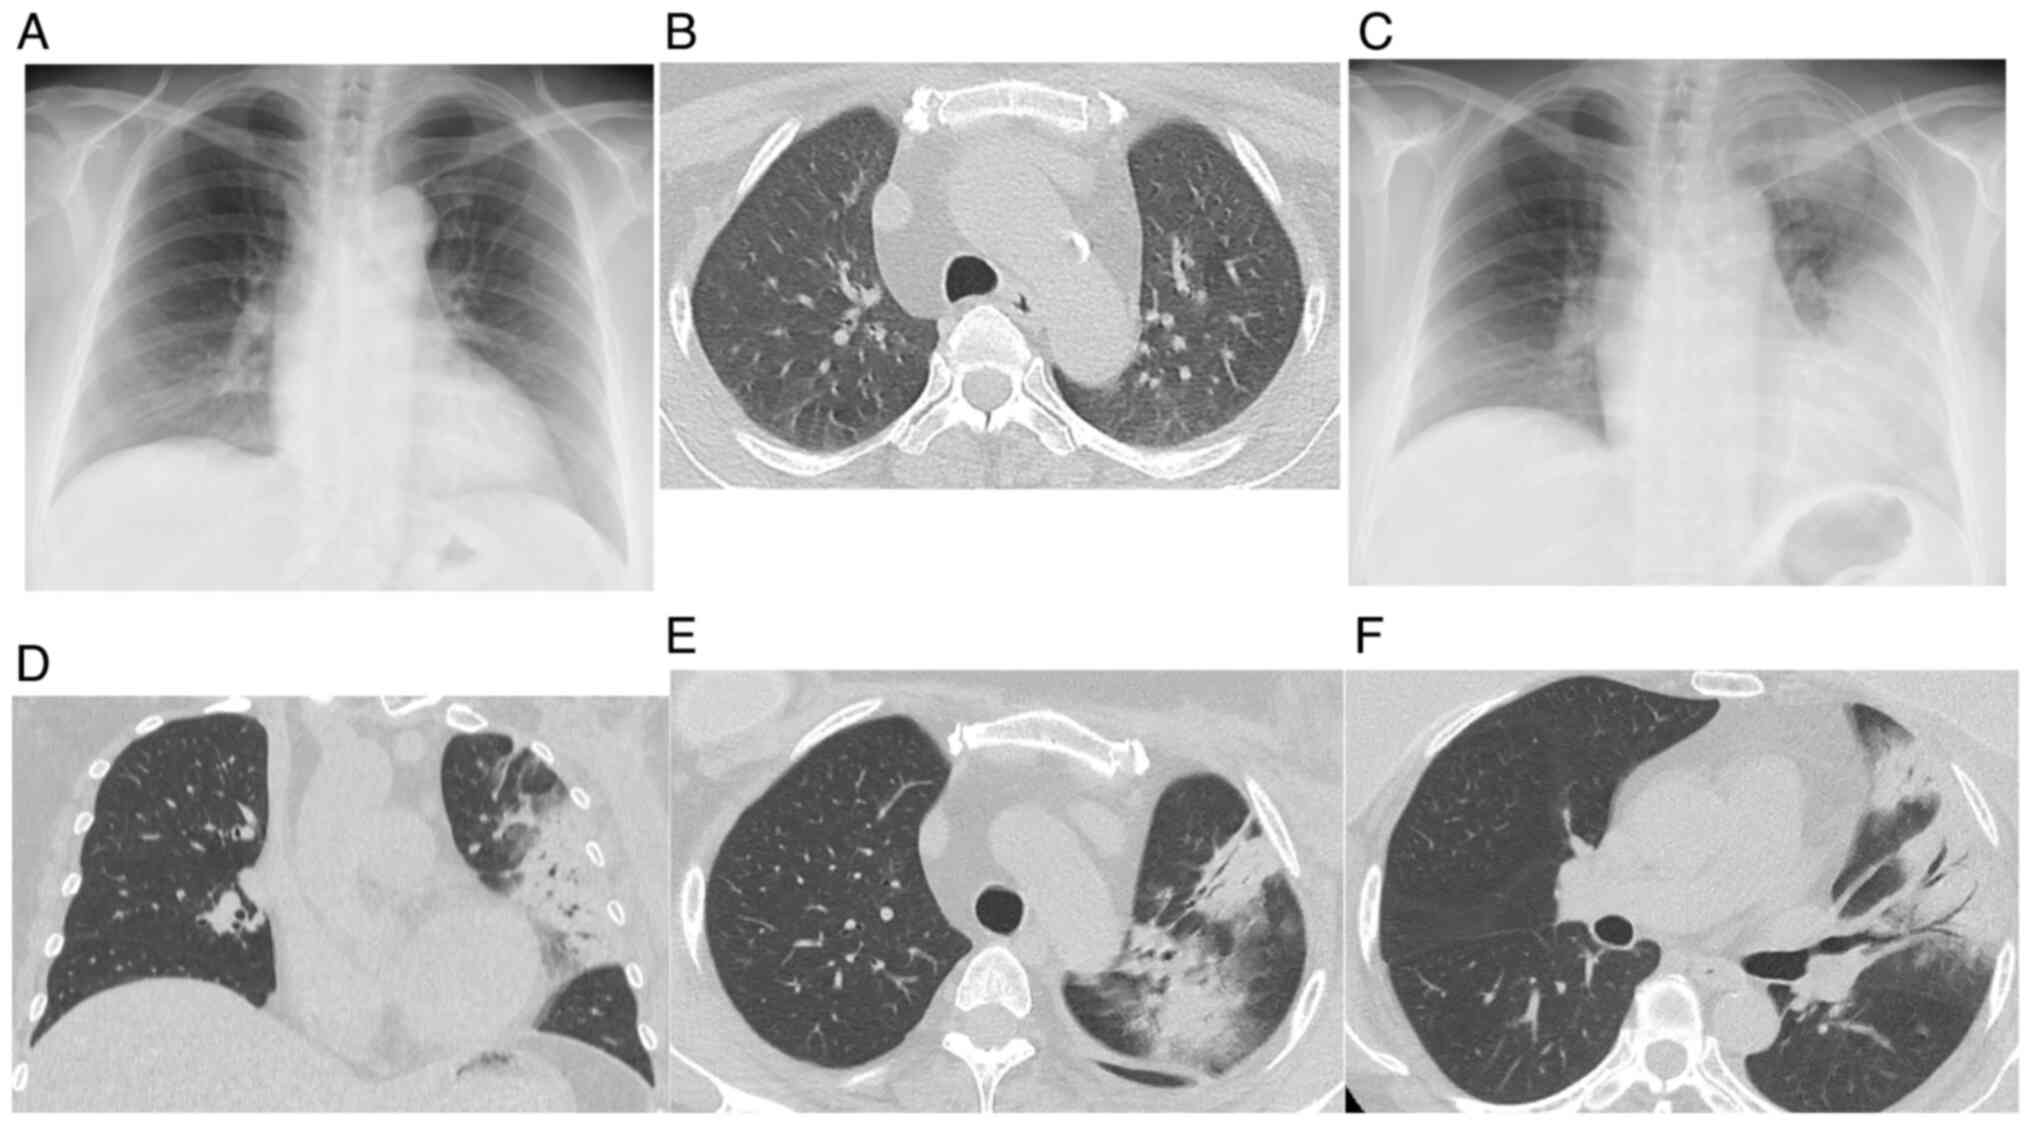

Figure 2

CT findings and chest radiograph findings. (A) Chest radiograph and (B) chest CT taken before the initiation of radiation therapy and abemaciclib treatment. (C) Chest radiograph revealing extensively decreased transparency throughout the left lung. Chest CT showing infiltrative shadows with bronchial transparency corresponding to the radiation-exposed area. (D) Coronal view. (E) Axial view. (F) Axial view.

A 52-year-old woman underwent left total mastectomy with axillary dissection and right total mastectomy for pT2N3aM0 stage IIIC breast cancer (left breast; invasive ductal carcinoma, estrogen receptor-positive, progesterone receptor-negative, Ki-67 25%) and pTisN0M0 stage 0 breast cancer (right breast; ductal carcinoma in situ, estrogen receptor-positive, progesterone receptor-positive, Ki-67 5%). Post-surgery, the patient received adjuvant therapy consisting of four cycles of dose-dense doxorubicin and cyclophosphamide chemotherapy, four cycles of dose-dense paclitaxel monotherapy, tamoxifen hormone therapy, and tangential irradiation therapy of 50 Gy in 25 fractions (Fig. 1). The radiation therapy caused erythema at the irradiation site, which improved after application of dimethyl isopropyl azulene ointment (dermatitis radiation grade 2). On day 366 after mastectomy and 20 days after the completion of radiation therapy, the adjuvant therapy with abemaciclib (300 mg/day) was initiated. On day 85 of abemaciclib treatment and 157 days after completion of radiation therapy, the patient presented with a history of cough, fever, and dyspnea for 1 week. CT findings were suggestive of interstitial pneumonitis (Fig. 2), and the patient was admitted for suspected drug-induced pneumonitis or radiation pneumonitis. The pneumonitis was classified as grade 3 according to the Common Terminology Criteria for Adverse Events, and abemaciclib was discontinued. Ampicillin/sulbactam treatment was initiated because bacterial pneumonia could not be ruled out.